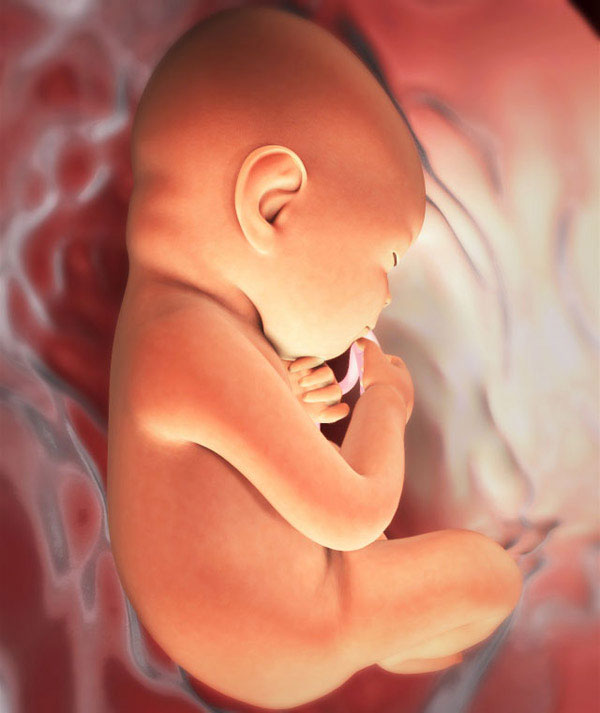

Le développement du fœtus

Au cours du premier trimestre de la grossesse, chaque semaine a apporté d'énormes changements dans le développement du fœtus. Maintenant, votre bébé a déjà formé tous les organes et systèmes. L'amélioration du cerveau et du système nerveux est la principale direction du développement ultérieur. Par exemple, le fœtus développe des terminaisons nerveuses. Cela signifie l'apparition d'une sensibilité générale et de la douleur. Les fibres nerveuses elles-mêmes, chaque jour, conduisent de mieux en mieux les signaux cérébraux vers les terminaisons nerveuses et vice versa. C'est un processus très compliqué, qui pour nous passe inaperçu, mais qui contrôle en fait toute notre vie.

Le bébé commence à développer des réactions protectrices naturelles. Par exemple, si maintenant avec un mouvement réflexe de la main, la came pénètre accidentellement dans l'œil, les paupières se fermeront spontanément pour protéger le globe oculaire.

De plus, le corps de l’enfant se prépare pour la vie à venir en dehors du corps de la mère. Le fœtus continue de développer de la graisse sous-cutanée. Grâce à cette substance, la peau du bébé perd progressivement une couleur rouge vif, elle devient légèrement plus pâle. Cependant, la couleur de la peau du bébé ne sera complètement déterminée que pendant un certain temps après l'accouchement. Il y a un lissage progressif de la peau, ce qui rend les nouveau-nés si joufflus.

Les traits du visage du fœtus deviennent plus définis, individuels. Les ongles poussent jusqu'au bout des doigts et leur croissance ne s'arrête pas là. De nombreuses mères sont frappées par la longueur des ongles de leur bébé à la naissance, mais en fait, c'est tout à fait normal.

À l'heure actuelle, de nombreux enfants sont déjà bien placés. La tête est en dessous, les fesses sous la poitrine de la mère, les bras et les jambes croisés et pressés contre le corps. Le port d'un bandage aidera le bébé à rester dans cette position et à ne pas se retourner.